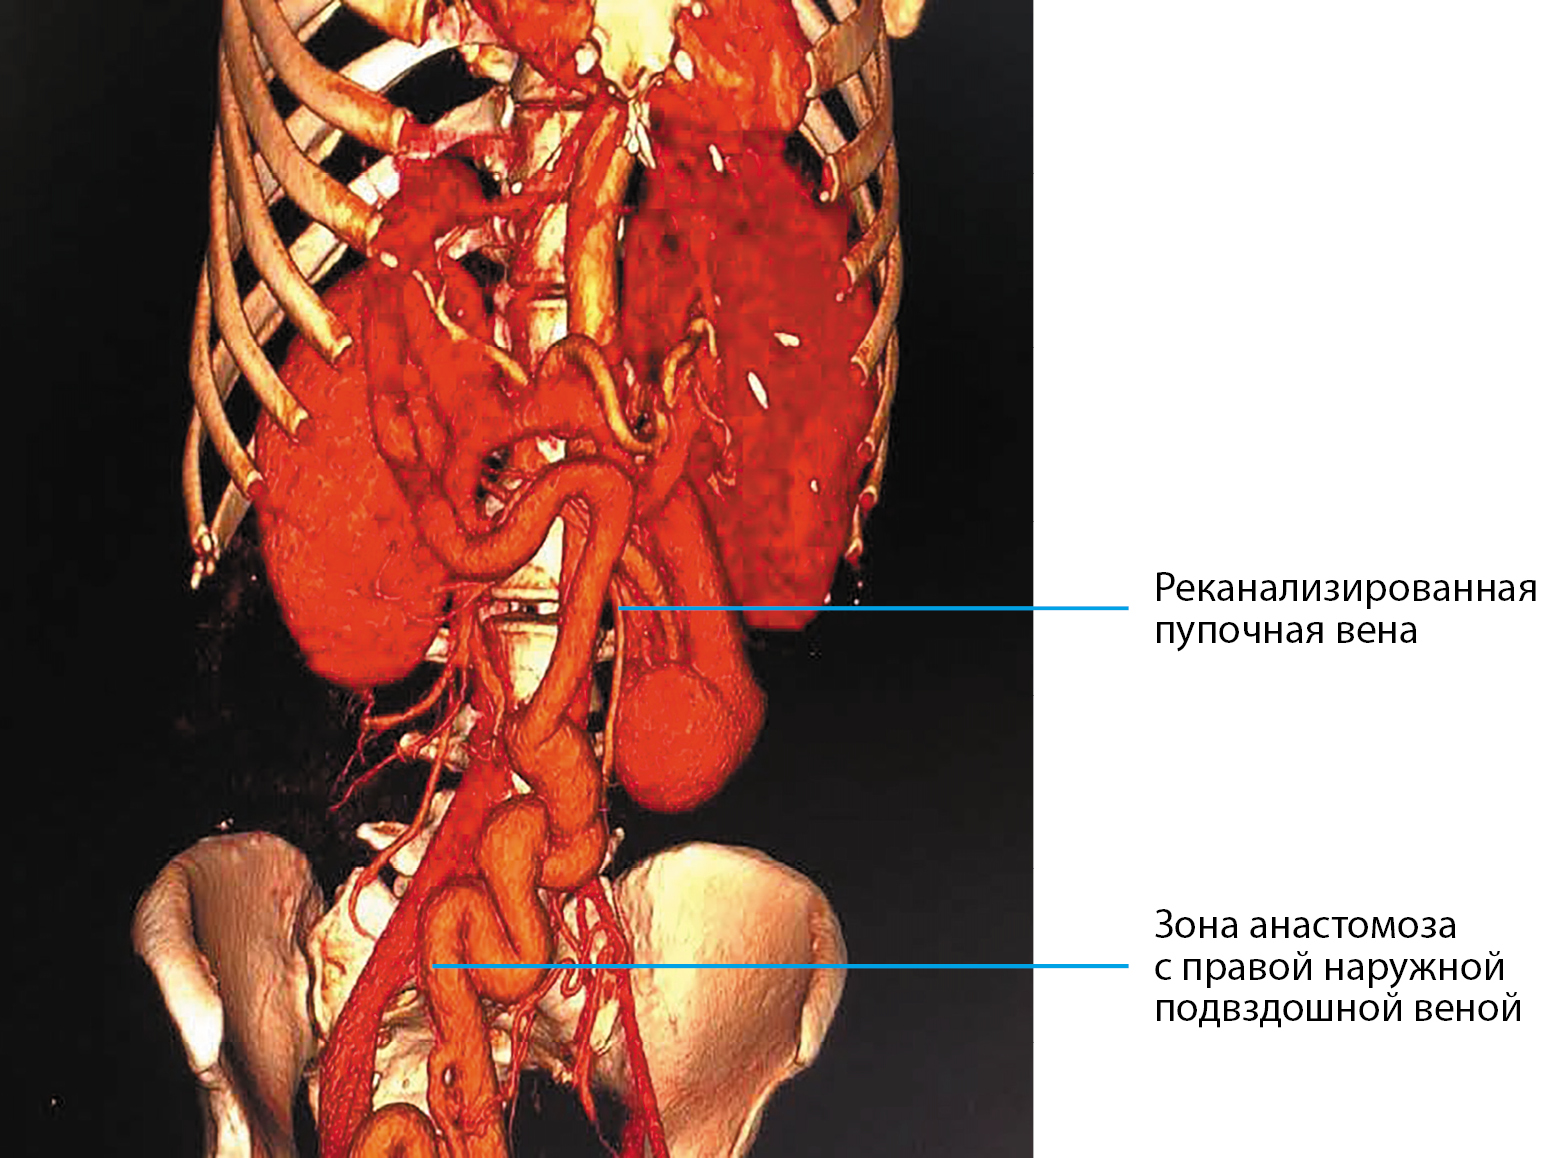

Пациентка Л., 49 лет (рост — 173 см, вес — 47 кг, ИМТ — 15,7 кг/м²) проконсультирована врачом-эндокринологом во время нахождения в отделении гепатологии и ОРИТ УКБ №2 ФГАОУ ВО ПМГМУ им. И.М. Сеченова в тяжелом состоянии. Известно, что длительное время наблюдается по поводу врожденного фиброза печени, портальной гипертензии, спленомегалии, ВРВП 1–2 ст. С 48 лет отметила появление болей в правом подреберье, сильно похудела (более 15 кг), стал увеличиваться в размерах живот, появились отеки ног. При компьютерной томографии органов брюшной полости — печень уменьшена в размерах, воротная вена — 22 мм, определяется анастомоз с варикозно расширенной сальниковой веной, правая и левая ветви окклюзированы, визуализируется реканализированная околопупочная вена диаметром 20 мм, впадающая в правую наружную подвздошную вену, визуализировались слабовыраженные спленогастральные, спленоренальные анастомозы. Также определялись расширенные легочные сосуды, спленомегалия и асцит (рис. 3). В это же время при обследовании выявлено повышение гликемии до 29 ммоль/л, диагностирован СД, начата инсулинотерапия. Назначенная инсулинотерапия включала в себя инсулин короткого действия внутривенно струйно под контролем гликемии. Отмечалась выраженная инсулинорезистентность, суточная доза инсулина составляла 150–200 ЕД (4,2 ЕД/кг), при этом меньшие дозы инсулина не позволяли достичь компенсации углеводного обмена.

Рисунок 3. Компьютерная томография органов брюшной полости пациентки Л.: печень уменьшена в размерах, воротная вена — 22 мм, формируется анастомоз с варикозно-расширенной сальниковой веной, правая и левая ветви окклюзированы.

Тяжесть состояния пациентки была обусловлена гипергликемией, портальной гипертензией с портосистемным шунтом, а также энцефалопатией. Портальная гипертензия, по всей видимости, была ассоциирована с врожденным фиброзом печени. В пользу этого говорит отсутствие анамнеза хронического заболевания печени, сохранная функция печени, компенсированная сформировавшимся портосистемным шунтом. Предполагается, что в развитие гипергликемии, выраженной инсулинорезистентности, энцефалопатии значительный вклад вносило наличие портосистемного шунта.